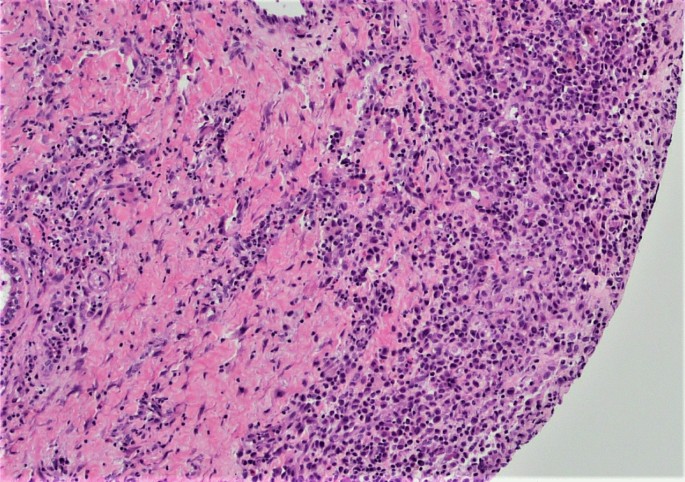

A punch biopsy was obtained at the intersection between the normal skin and the perianal rash during this initial visit. He was prescribed 1% zinc oxide cream to apply to the perianal skin for symptomatic management of pruritus three times daily. Pathology showed atypical plasmacytoid appearing cells in the deep dermis layer with mild-to-moderate nuclear atypia, mixed with a benign-appearing lymphoplasmacytic population with occasional eosinophils. The atypical cells were positive for S-100, CD1a, CD68, and Langerin, with a Ki-67 index of 50% (Figs. 1, 2, 3, 4, 5, 6, 7). These cells were negative for BRAF V600E mutations, CD3, CD20, carcinoma, and melanoma markers. Based on these results, he was diagnosed with a Langerhans cell neoplasm.

As the prognosis and respective treatments of LCH and LCS differ, it is important to obtain a sufficient biopsy sample to make a definitive diagnosis. Few studies have detailed specific parameters that differentiate LCS and LCH. Pileri et al.’s study of histiocytic tumors showed that LCH had mild-to-moderate nuclear atypia with benign-appearing nuclei, while LCS had frank malignant cytologic features with more prominent nucleoli [29]. Ki-67, a cellular proliferation marker, of the patient was elevated (50%), but he had mild atypia with no significant pleomorphism. This cellular morphology is consistent with a benign proliferation, but as biopsy was of limited size from the edge of the lesion, it is not possible to know the extent of cytologic malignant features, if present, and definitively exclude the possibility of LCS.